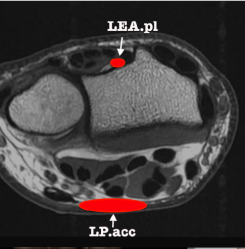

1/ Muscle accessoire de l'abducteur du V pouvant venir comprimer le nerf ulnaire

4/ insertion aberrante du fléchisseur du V pouvant venir comprimer le nerf ulnaire